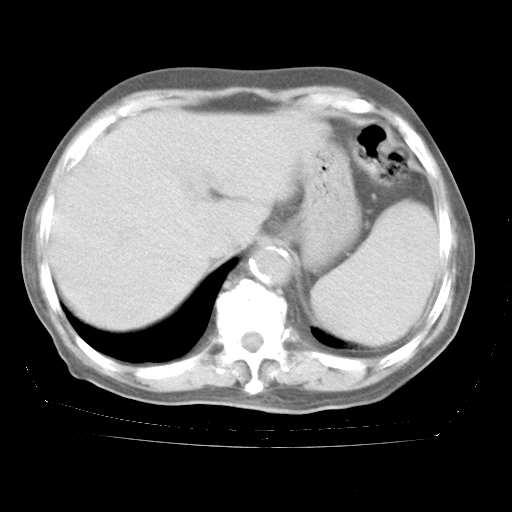

4月28日肺部CT